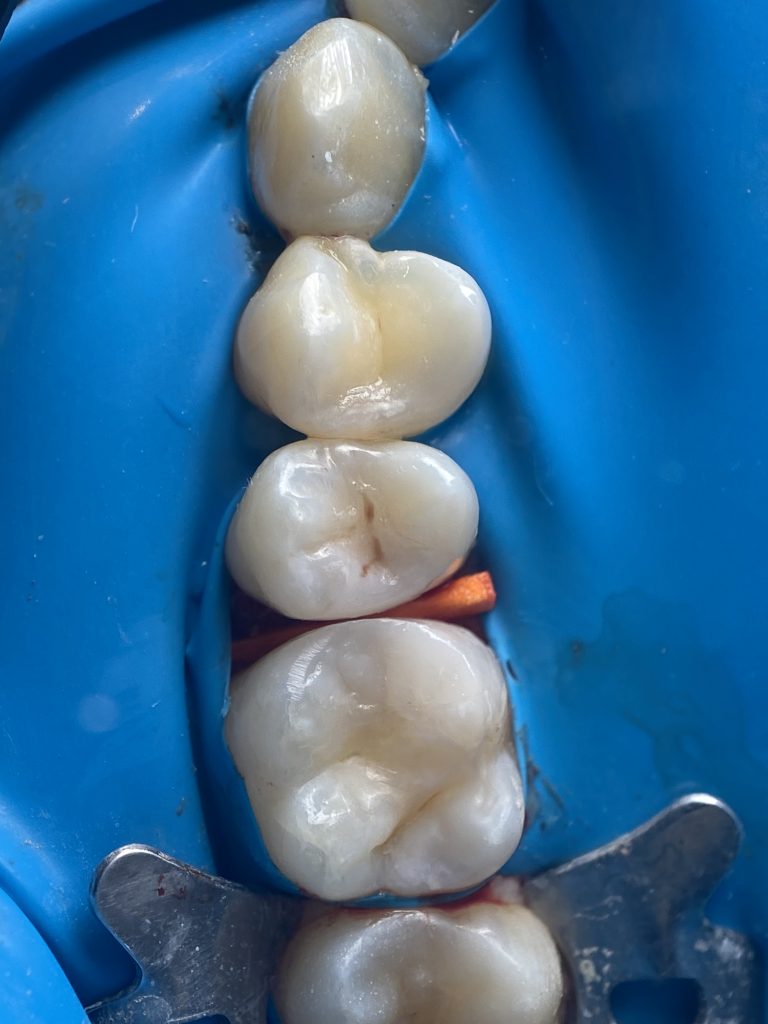

-MTA application

-Distal wall elevation